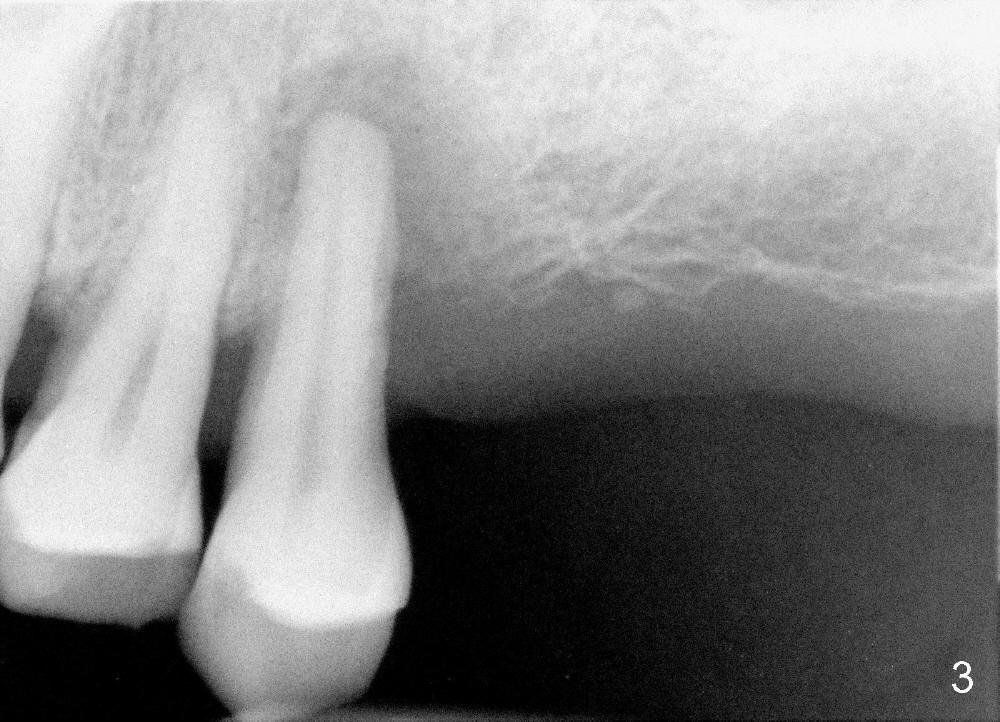

Fig.3 is a PA taken 2 years preop, whereas Fig.4 immediately preop showing purulent discharge from the distal gingival sulcus (*). When the tooth is extracted, the socket is rounded, favoring placement of a rounded implant instead of D-shaped implant. The coronal opening of the socket is ~ 8x8 mm. Granulation tissue is removed from the buccal and distal aspects of the socket.